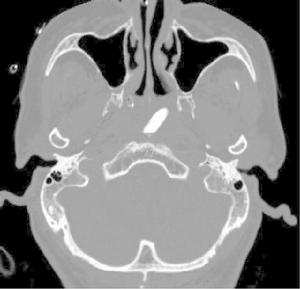

顱腦CT檢查技術

1.檢查方法及掃描參數 急性腦出血、腦先天性畸形、腦積水、腦萎縮、診斷明確的腦梗死只做平掃。腫瘤術後複查可做直接增強掃描。顱內腫瘤、感染、腦動脈瘤和血管畸形、寄生蟲病、多發性硬化做平掃和增強掃描。

(2)窗位:L30~40HU,窗寬:W70~100HU。

(3)骨窗窗位:L300~500HU,窗寬:W1300~1800HU。